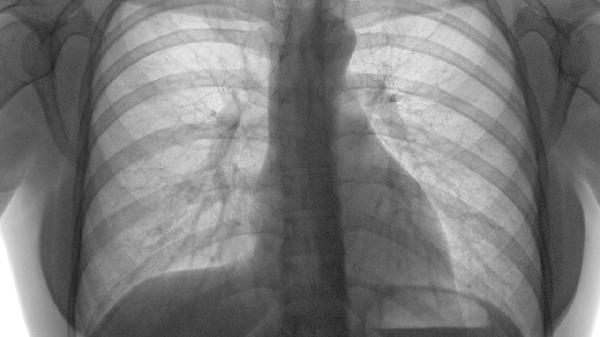

骨折端未完全愈合或错位愈合可能导致持续性疼痛。陈旧性肋骨骨折若存在骨痂形成异常或假关节活动,会在呼吸、咳嗽时产生牵拉痛。建议通过影像学检查评估愈合情况,必要时采用肋骨固定术或镇痛治疗,如使用洛索洛芬钠片、塞来昔布胶囊等非甾体抗炎药。